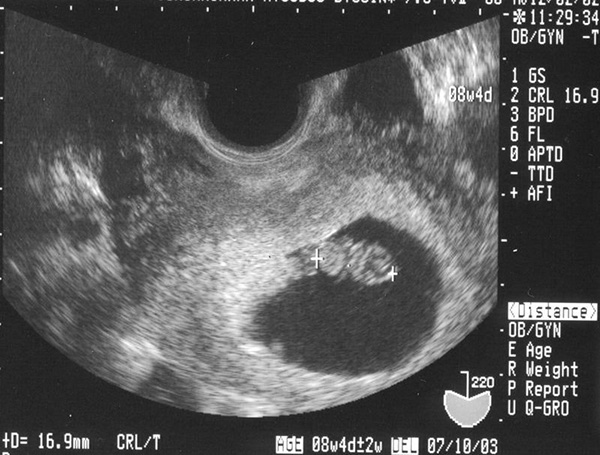

Có một vài trường hợp chị em xuất hiện tình trạng đau mạnh và co bóp ở tử cung và kèm theo ra máu thì có thể chị em đang có thai ngoài tử cung. Lúc này, chị em cần phải đến các cơ sở y tế để được thăm khám và và tìm ra nguyên nhân của việc này.

Trường hợp các chị em không thấy có những dấu hiệu thai vào tử cung như nêu trên mà lại có những hiện tượng bất thường trong giai đoạn đầu như: đau bụng dữ dội, lượng kinh nguyệt ra nhiều thì lúc này cần tới các cơ sở y tế để khám bệnh.

Bởi, rất có thể chị em đang gặp phải hiện tượng mang thai ngoài tử cung hay nhiều vấn đề nguy hiểm khác. Vì vậy, dù bất cứ một dấu hiệu bất thường nào khác hãy đến ngay phòng khám hoặc bệnh viện để được khám và tìm ra nguyên nhân.